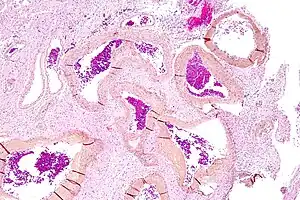

Micrograph of an arteriovenous malformation in the brain. HPS stain.